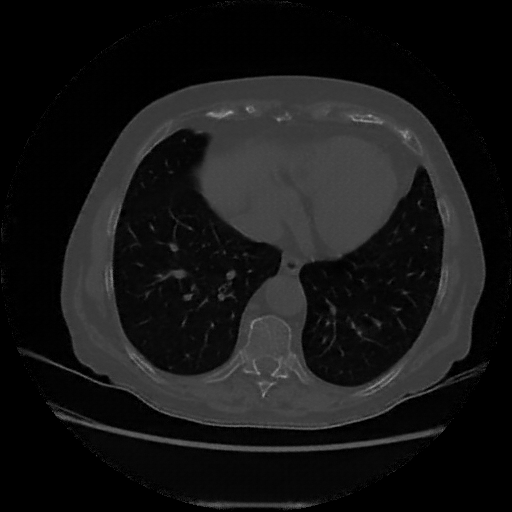

Targeted Slice 70 - Lung Window Analysis (Generated vs Real Venous)

0.654

Lung SSIM

173.9

Lung RMSE

69.6

Lung MAE

Average Lung Window Metrics Across All Slices (107 slices) - Generated vs Real Venous

0.678

Lung SSIM (Avg)

137.1

Lung RMSE (Avg)

56.3

Lung MAE (Avg)

Lung window (WL -600, WW 1500 β†’ Low βˆ’1350, High +150)

Reconstructed NATIVE CT scan (cycle consistency)

Generated VENOUS CT scan (A→B translation)